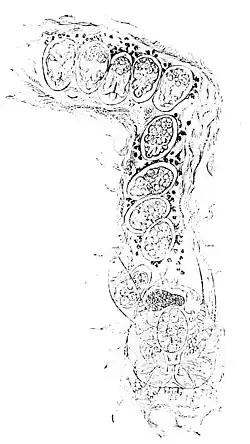

Fig. 12.—Burrow of Itch-Insect (Sarcoptes scabei).—Female depositing eggs. The eggs lying next to the insect consist partly of an homogeneous, partly of a granular mass: in those distant from the insect embryos are already developed, and at the entrance of the furrow a moving acarus is seen.

of warmth, so that it lies dormant during the day, when the body is cool, to sally forth in search of new fields when stimulated by the genial warmth of the bed. This explains also why the itching is most violent at night. The mode of getting rid of the parasite is obvious; we have only to kill it; and, fortunately, the means is cheap, easily applied, and perfectly effectual: sulphur, which seems to be a deadly bane to all insects, in whatever shape it can be given. It is only necessary to expose the insect to its influence, and it surely dies.